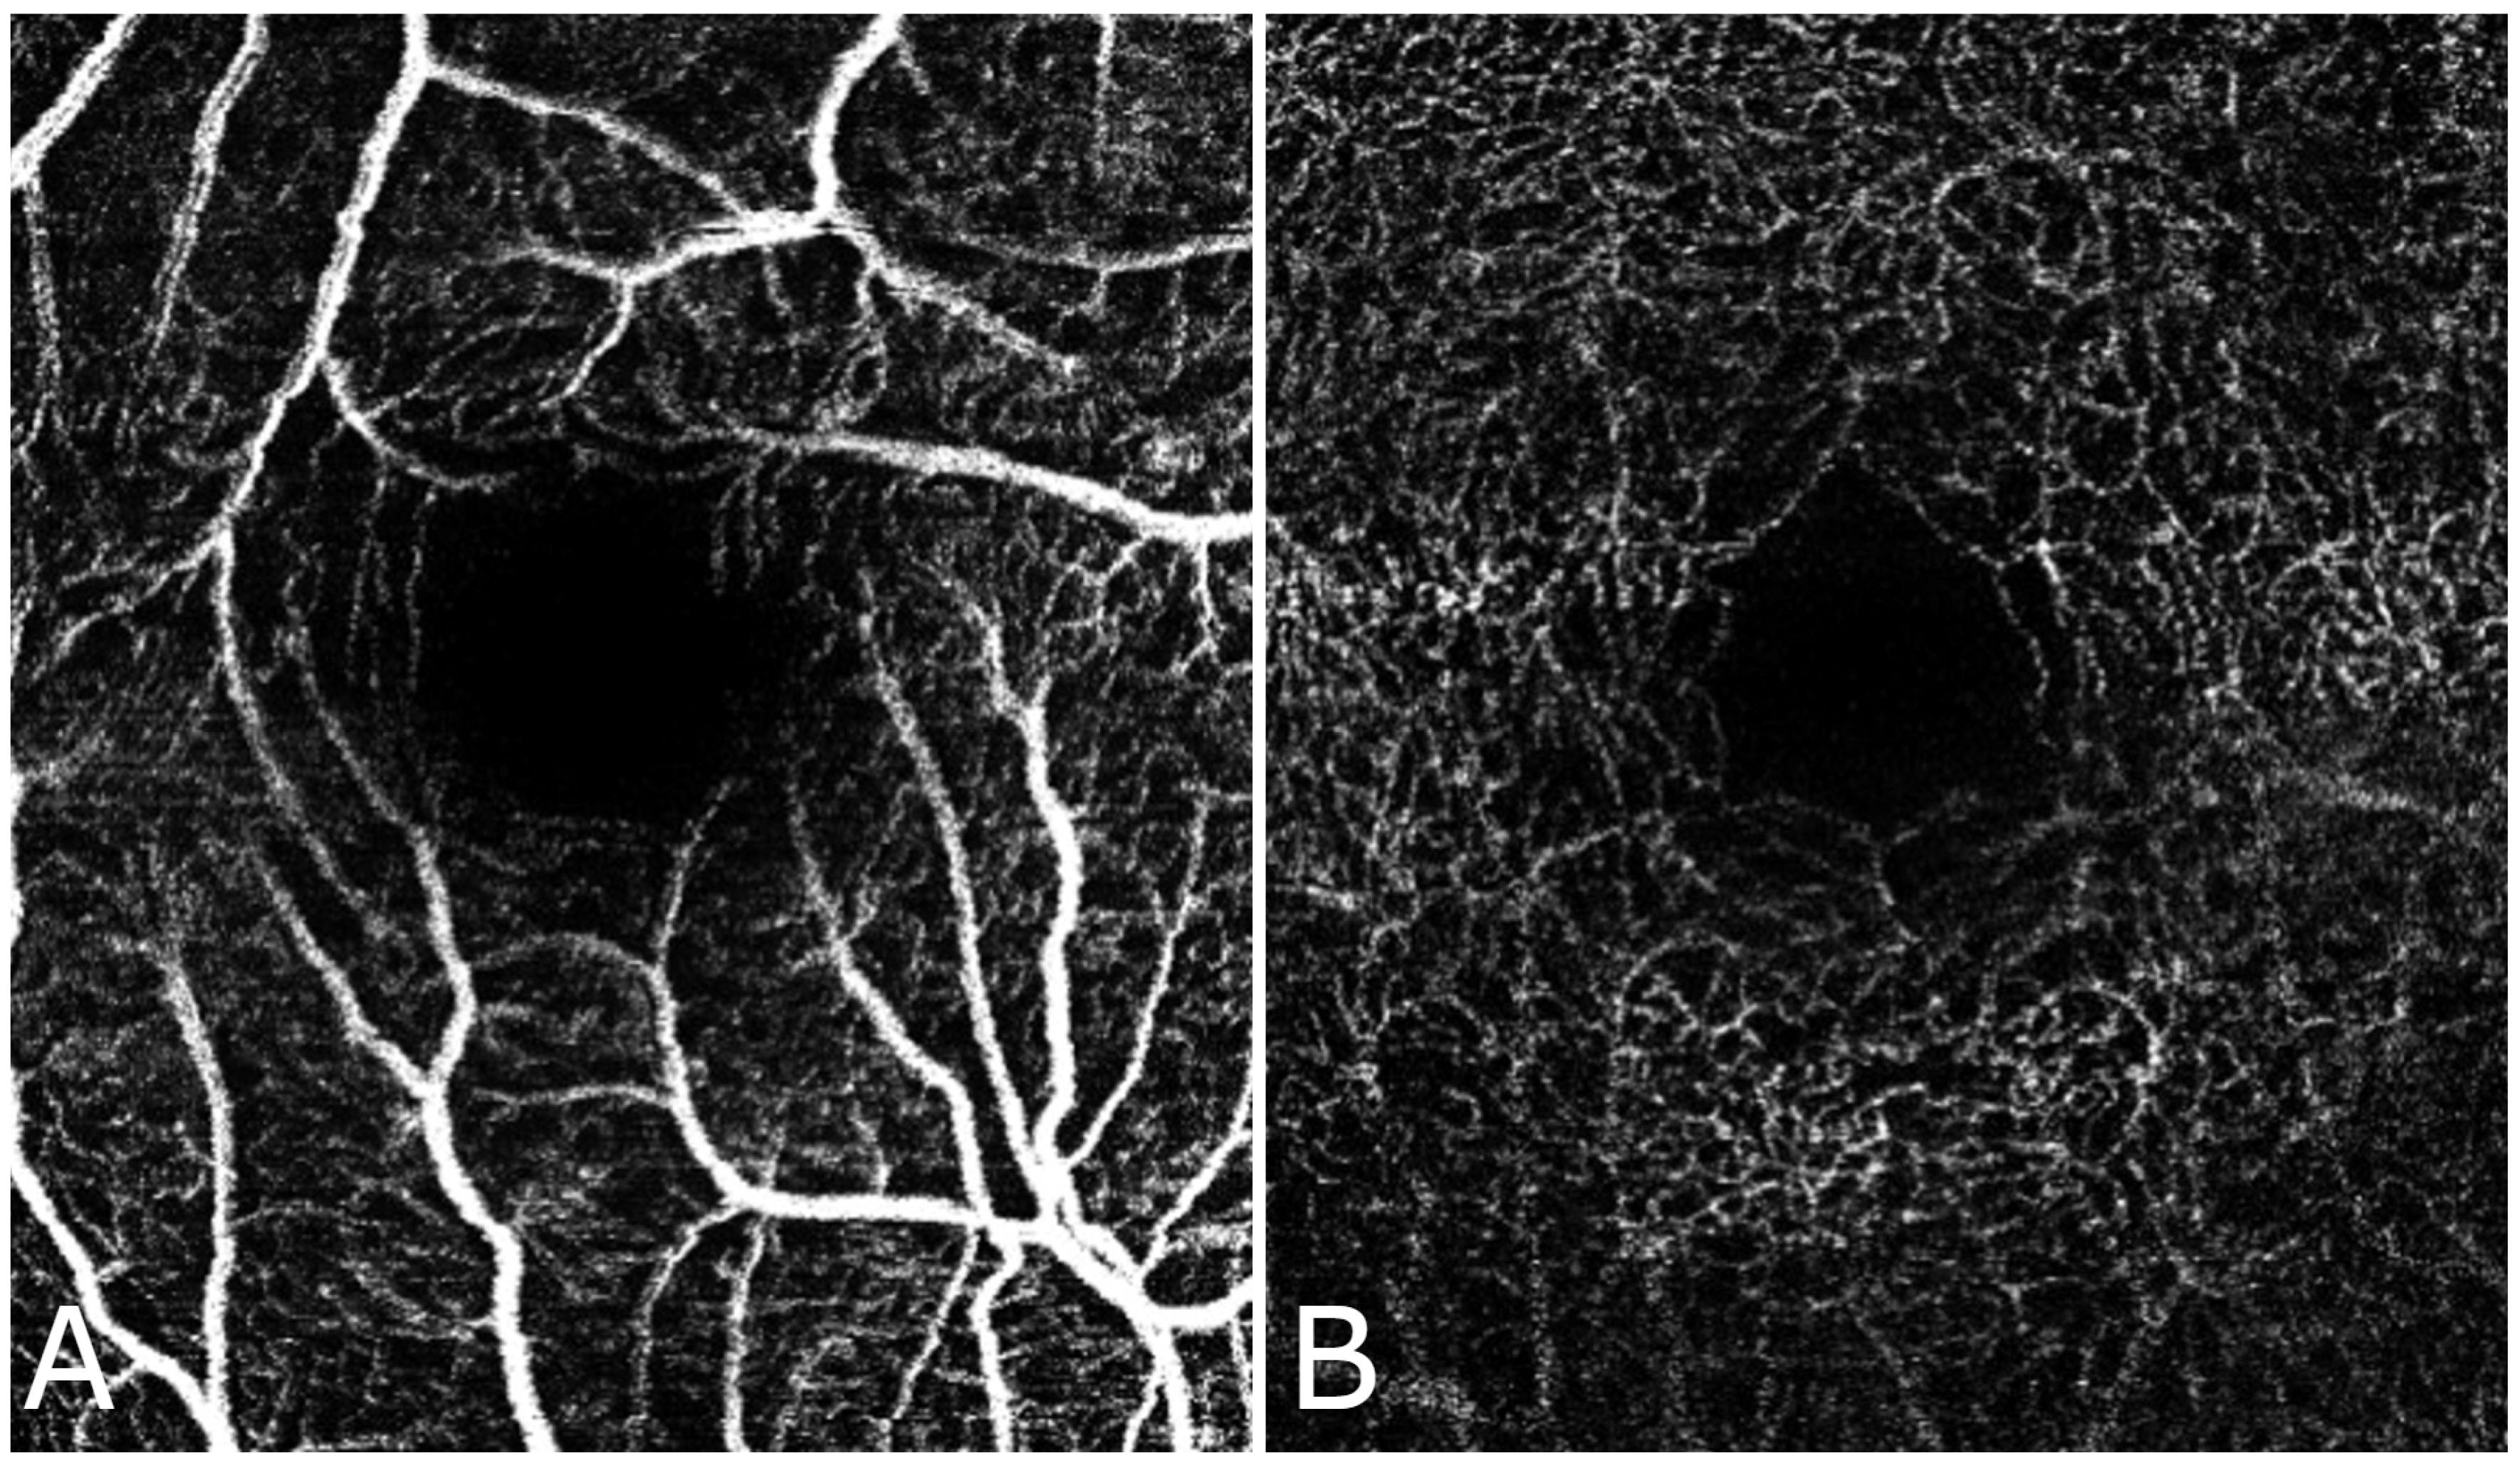

Both superficial and deep FAZ areas were significantly larger in diabetic patients compared to controls (p < 0.05), indicating vascular alterations associated with diabetes. The mean superficial FAZ value for the diabetes group was 0.37 mm2 (SD = 0.17 mm2, range = 0.20–0.53 mm2) and 0.26 mm2 (SD = 0.08 mm2, range = 0.19–0.35 mm2) for the deep FAZ. For the control group, the superficial FAZ was 0.21 mm2 (SD = 0.07 mm2, range = 0.20–0.32 mm2) and deep FAZ was 0.18 mm2 (SD = 0.06 mm2, range = 0.14–0.16 mm2). The 95% confidence interval (CI) for the superficial FAZ value in the DM group was 0.21–0.53 mm2 and 0.12–0.32 mm2 for the control group. For deep FAZ, the 95% CI in the DM group was 0.20–0.31 mm2, while for the control group, it was 0.12–0.28 mm2. Figure 2 and Figure 3 shows the FAZ in the control group (A) is smaller and well-defined, while in the diabetic group (B), the FAZ is larger and irregular, reflecting the vascular changes associated with diabetic retinopathy. Table 1 presents the FAZ area measurements (in mm2) for both superficial and deep capillaries in both groups.

Figure 2. OCT angiography: FAZ area in the deep (A) and superficial (B) vascular plexus in a healthy individual. Scale bar = 200 µm.